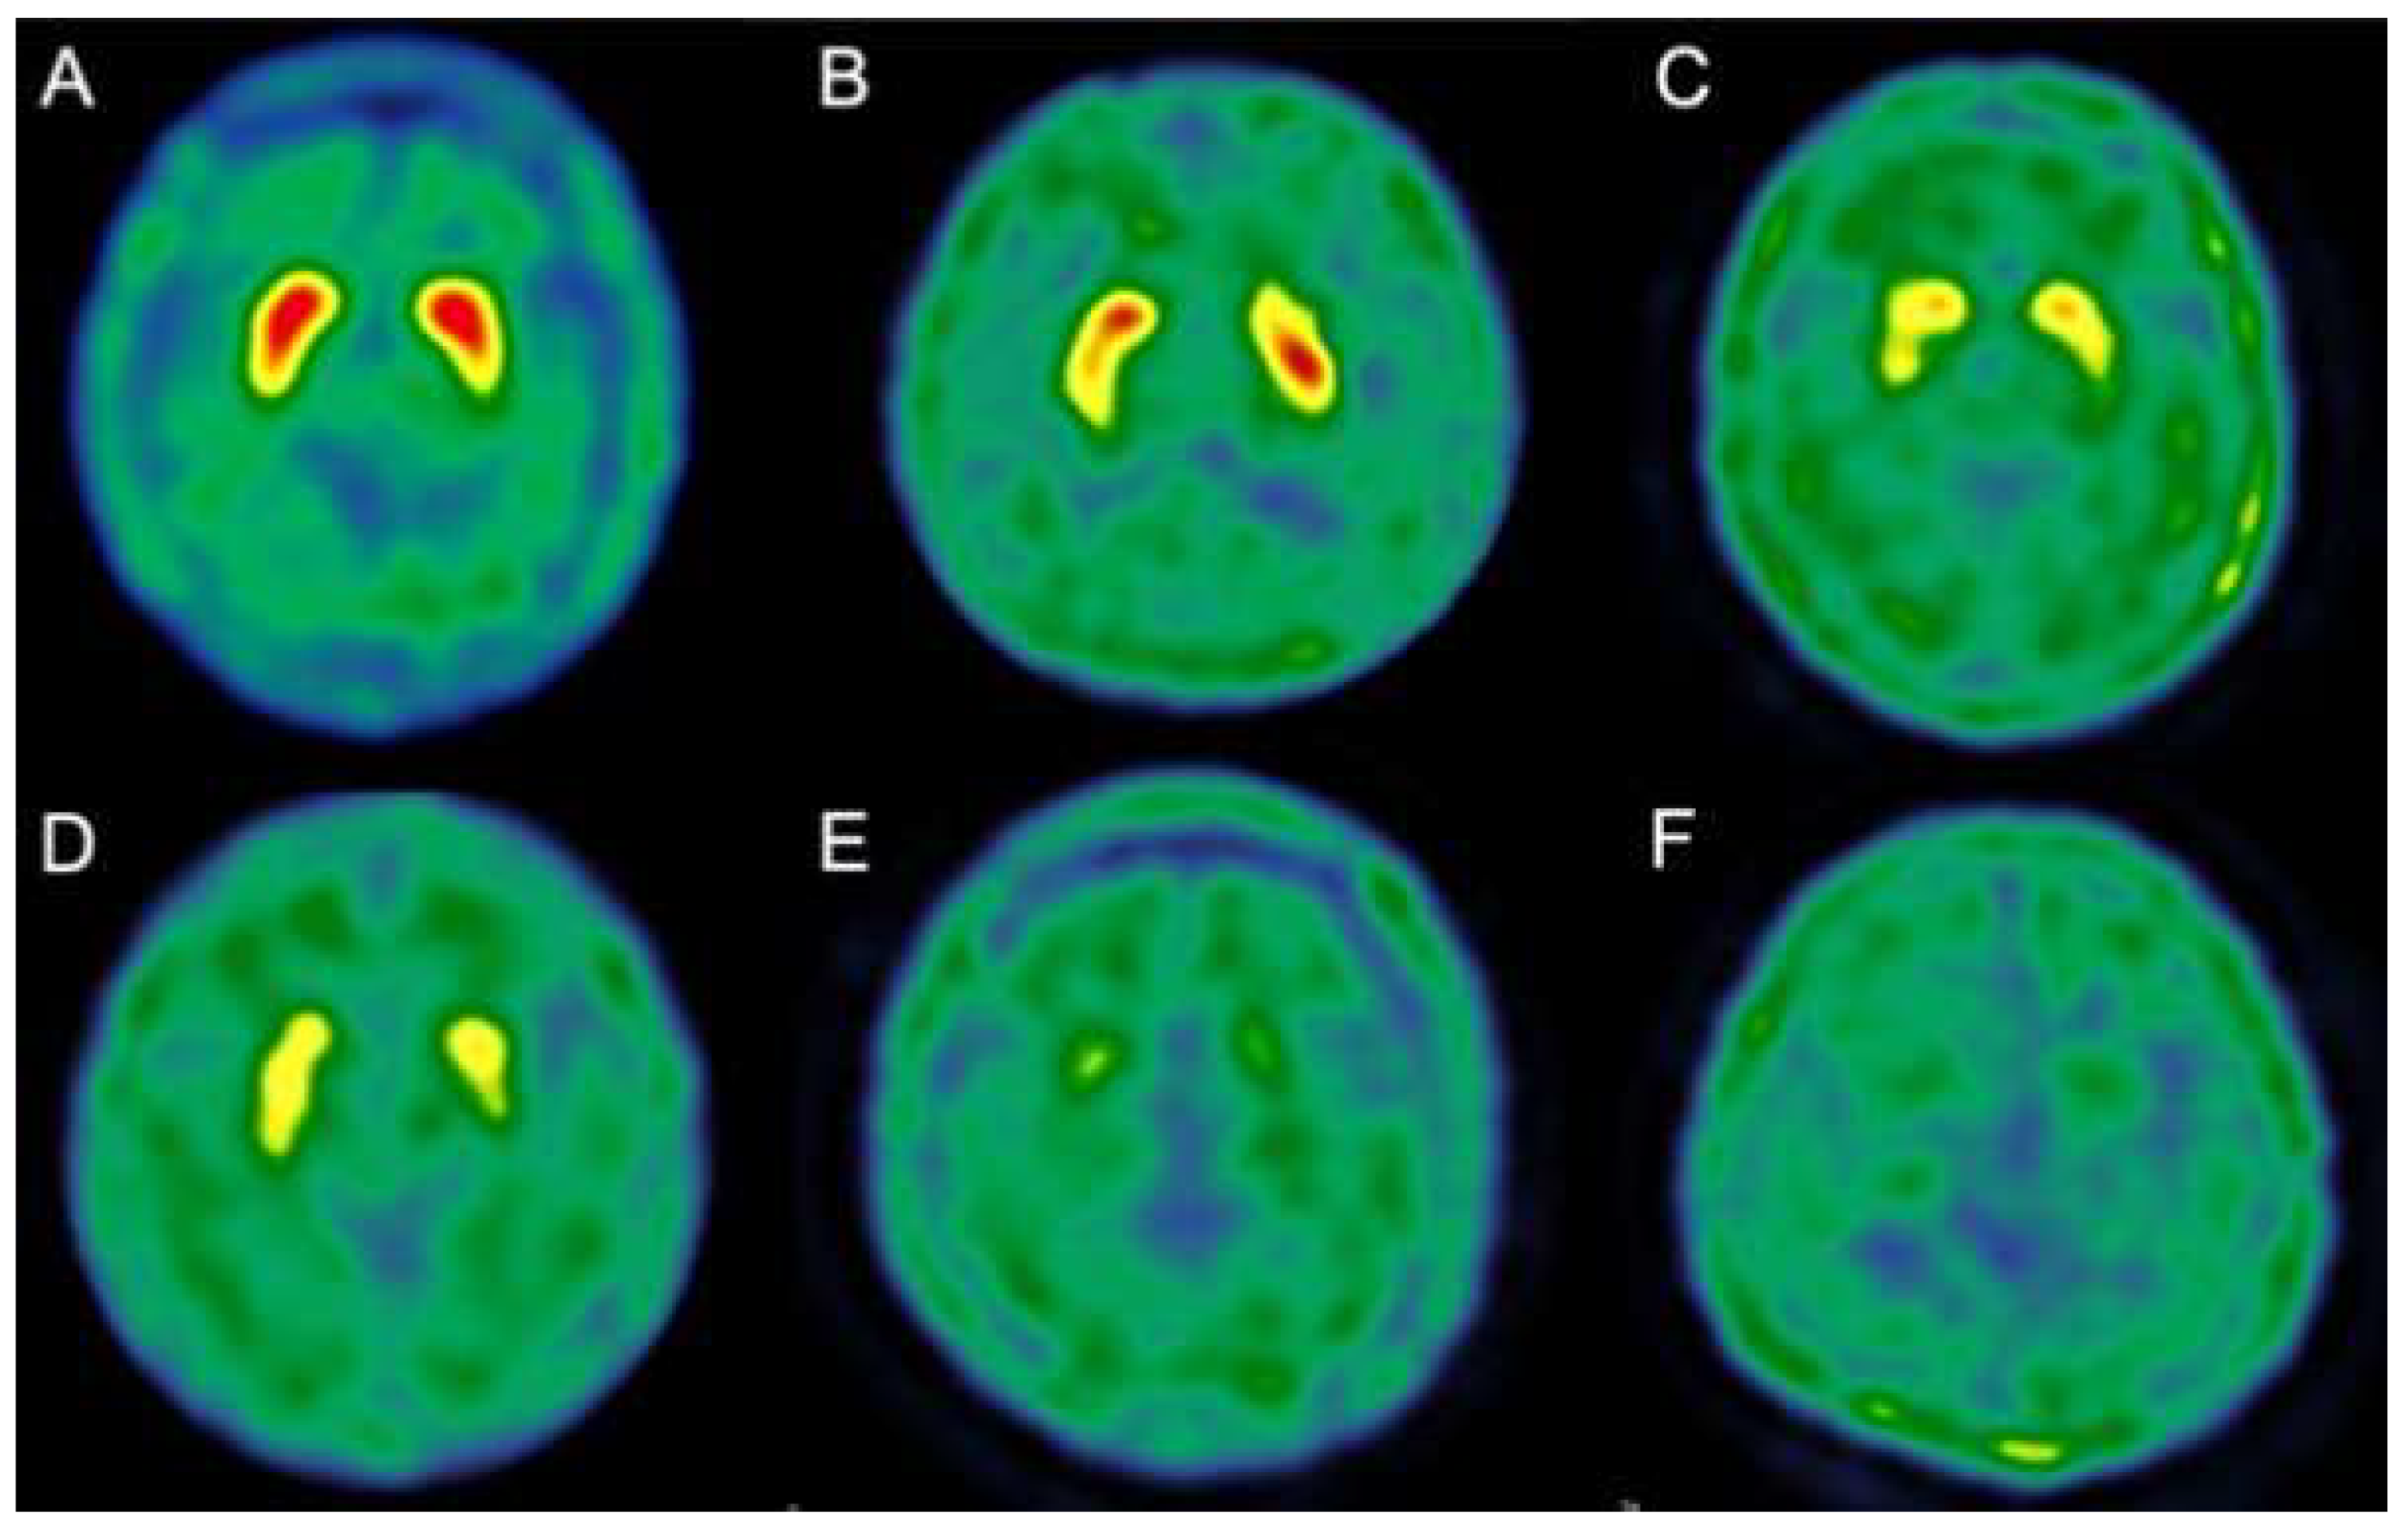

2.2.2. 99 mTc-TRODAT-1 SPECT

- Shyu, W.-C.; Lin, S.-Z.; Chiang, M.-F.; Pang, C.-Y.; Chen, S.-Y.; Hsin, Y.-L.; Thajeb, P.; Lee, Y.-J.; Li, H. Early-onset Parkinson’s disease in a Chinese population: 99mTc-TRODAT-1 SPECT, Parkin gene analysis and clinical study. Parkinsonism Relat. Disord. 2005, 11, 173–180. [Google Scholar] [CrossRef]

- Huang, W.S.; Lin, S.Z.; Lin, J.C.; Wey, S.P.; Ting, G.; Liu, R.S. Evaluation of early-stage Parkinson’s disease with 99mTc-TRODAT-1 imaging. J. Nucl. Med. 2001, 42, 1303–1308. [Google Scholar]